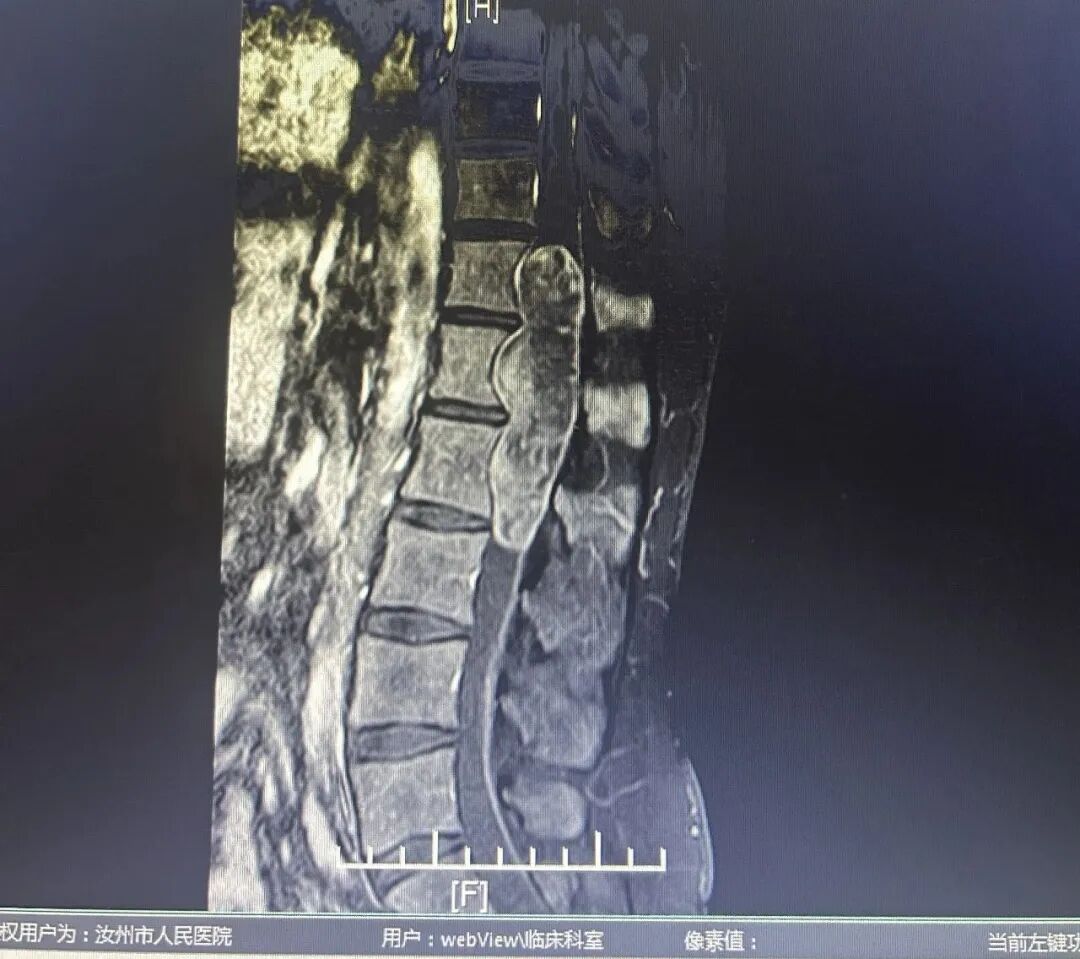

经检查发现小张胸椎、腰椎多阶段椎管内肿瘤,考虑畸胎瘤,并且肿瘤横跨胸椎和腰椎四个椎体,长度约13厘米,横径3.5厘米,肿瘤严重压迫脊髓

如果不及时切除肿瘤,拆除“炸弹”,患者将面临瘫痪的巨大风险。

胸椎、腰椎肿瘤形状酷似巨型毛毛虫